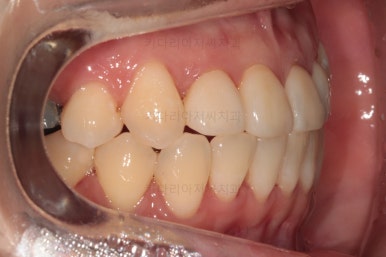

옆모습 중간중간 체크해 주고요.

이번 환자분은 옆라인이 애초에 매우 좋으셨기 때문에 입매를 바꾸지 않아야해서 오히려 더 세심한 치료가 필요한 환자분이셨습니다.

공간을 줄여나가고 순차적으로 충치치료도 마무리 해갑니다.

교합이라던가 부족한 부분을 좀 더 마무리하고요.